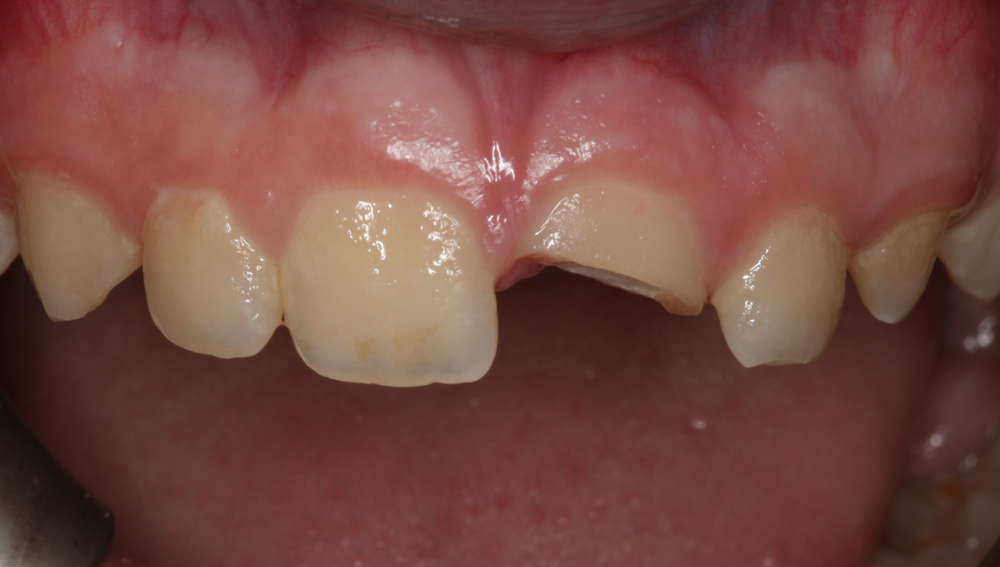

Fortunately, the patient’s mother had retained the missing, fractured tooth segment (Fig. 3). Therefore, the treatment plan discussed with and accepted by the patient’s parents involved reattaching the fractured tooth segment using a universal dual-cure adhesive resin cement, G-CEM LinkForce, after which a compactable universal nano-hybrid composite, G-ænial Sculpt would be placed to directly veneer the facial and palatal surfaces of the tooth to mask the fracture line (Fig. 4).

Fig. 3 Fig. 4